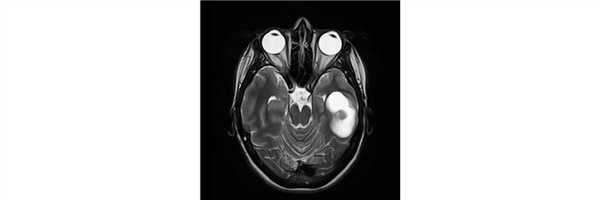

При МРТ выявлена опухоль левой височной доли с небольшим кистозным компонентом.

Пациентке проведена операция - микрохирургическое удаление внутримозговой опухоли левой височной доли

Гистологический диагноз - анапластическая плеоморфная ксантоастроцитома WHO grade III, BRAF-позитивная.

В послеоперационном периоде появления неврологического дефицита не отмечено.

При контрольной СКТ данных за остатки опухолевой ткани/ послеоперационные осложнения не получено.

Пациентка выписана на 7 сутки после операции.

В послеоперационном периоде проводилась лучевая, химиотерапия и таргетная терапия.